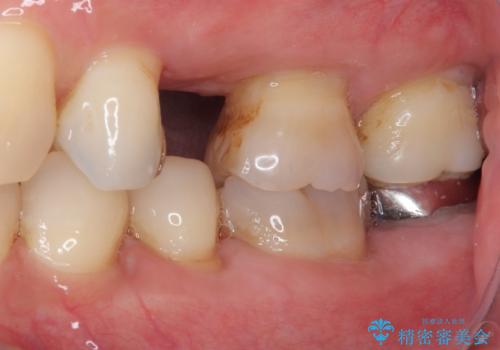

インプラント埋入時に十分な安定性が確認できたため、当日仮歯を装着しました。

埋入から2ヶ月ほどでインプラントの十分な生着が認められ、処置した歯肉も綺麗に治癒したため、速やかに補綴治療を行いました。